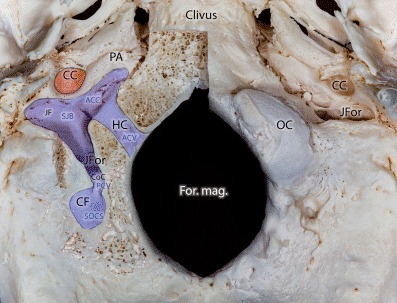

Fig. 1.

Bony relations of the occipital condylar region on the external cranial base. On the right side of the specimen the occipital condyle was partly removed to show the entire length of the hypoglossal and condylar canals as well as their junction around the jugular fossa. ACC anterior condylar confluence, ACV anterior condylar vein, CC carotid canal, CF condylar fossa, CoC condylar canal, For. mag. foramen magnum, HC hypoglossal canal, ICA internal carotid artery, JF jugular fossa, JFor jugular foramen, OC occipital condyle, PA petrous apex, PCV posterior condylar vein, SJB superior bulb of the internal jugular vein, SOCS suboccipital cavernous sinus

The posterior condylar vein (PCV), which is an emissary vein connecting the extracranial and intracranial venous system (Figs. 1 and 2a, b), runs through the CoC. Extracranially the PCV originates from the suboccipital cavernous sinus (SOCS), which is located within the condylar fossa. Intracranially the PCV drains into the SJB.

The anterior condylar vein (ACV) is located within the hypoglossal canal (HC) and passes through the occipital condyle mediolaterally, perpendicular to the longer axis of the condyle (Fig. 1). The intracranial end of the ACV is connected to the area of the anterior internal vertebral venous plexus (AIVVP), basilar plexus and the marginal sinus (Fig. 3a). The extracranial ending of the ACV terminates in the anterior condylar confluence (ACC). The ACC is a venous pouch located at the extracranial opening of the hypoglossal canal and drains directly into the SJB. The HC and the CC as well as the ACV and PCV within them are situated nearly perpendicularly to each other (Fig. 3a).

The HC is an intraosseous canal on both sides of the foramen magnum cranially to the occipital condyle. It contains the hypoglossal nerve, the neuromeningeal branch of the ascending pharyngeal artery and the anterior condylar vein [3, 5, 10]. The ACV is a venous plexus that surrounds the hypoglossal nerve whilst it traverses the HC [5, 10]. It links the ACC to the anterior internal venous vertebral plexus (AIVVP) (Figs. 1 and 3a). Furthermore, connections to the basilar plexus are infrequently observed. In angiograms, the ACV, and hence DAVFs of the ACV and the ACC are found immediately medially, inferiorly and anteriorly to the jugular bulb (Figs. 3c and 5b).

The CoC is an intraosseous canal that connects the dorsal aspect of the jugular foramen with the condylar fossa and terminates directly dorsal to the occipital condyle [11]. Within the CoC run the PCV and meningeal branches of the occipital artery. The PCV originates from the bulb of the jugular vein, the most medial point of the sigmoid sinus or the ACC (Fig. 4b; [10, 12, 13]). It terminates in the vertebral artery venous plexus (VAVP) or deep cervical veins (DCV). As one of the largest emissary veins the PCV is an important anastomosis between the intracranial and extracranial venous systems. In angiograms, the posterior condylar vein and hence also fistulas of the PCV can be found dorsally and posteriorly to the bulb of the internal jugular vein (Fig. 4a; [10]).